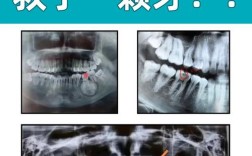

- 曲面体层片: 观察全口牙列、颌骨、上颌窦、颞下颌关节等。

- 翼片/根尖片: 观察邻面龋、牙周状况。

- CBCT: 精确观察复杂牙根形态、根管、骨缺损、囊肿、肿瘤等三维结构。